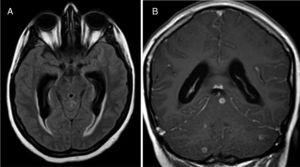

We present the case of a 23-year-old immunocompetent Berber woman who, after a second caesarean section with epidural anaesthesia, presented headache, neck rigidity, and subacute nausea progressing for 2 weeks; fever was not observed. A brain computed tomography scan showed normal findings, but a subsequent lumbar puncture revealed thick cerebrospinal fluid with low glucose levels, lymphocytic pleocytosis, and elevated adenosine deaminase (ADA) activity. A chest radiography revealed no abnormalities. Several hours after starting empirical treatment with tuberculostatic drugs (isoniazid 300 mg + pyrazinamide 1600 mg + rifampicin 600 mg + ethambutol 1100 mg/day, orally) and steroids (dexamethasone 4 mg/8 h), the patient presented neurological impairment with confusional symptoms, paraparesis of the lower limbs and anaesthesia from T10, and urinary retention. Neuroaxial magnetic resonance imaging (MRI) revealed communicating hydrocephalus, brain and spinal meningeal enhancement, posterior fossa tuberculomas, and a spinal extra-axial contrast-enhanced lesion at the T10 level suggestive of epidural abscess (Figs. 1 and 2). We observed no vertebral involvement. The Löwenstein-Jensen medium yielded positive results for Mycobacterium tuberculosis.